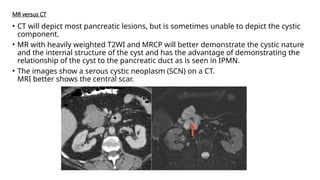

MR versus CT

• CT will depict most pancreatic lesions, but is sometimes unable to depict the cystic

component.

• MR with heavily weighted T2WI and MRCP will better demonstrate the cystic nature

and the internal structure of the cyst and has the advantage of demonstrating the

relationship of the cyst to the pancreatic duct as is seen in IPMN.

• The images show a serous cystic neoplasm (SCN) on a CT.

MRI better shows the central scar.